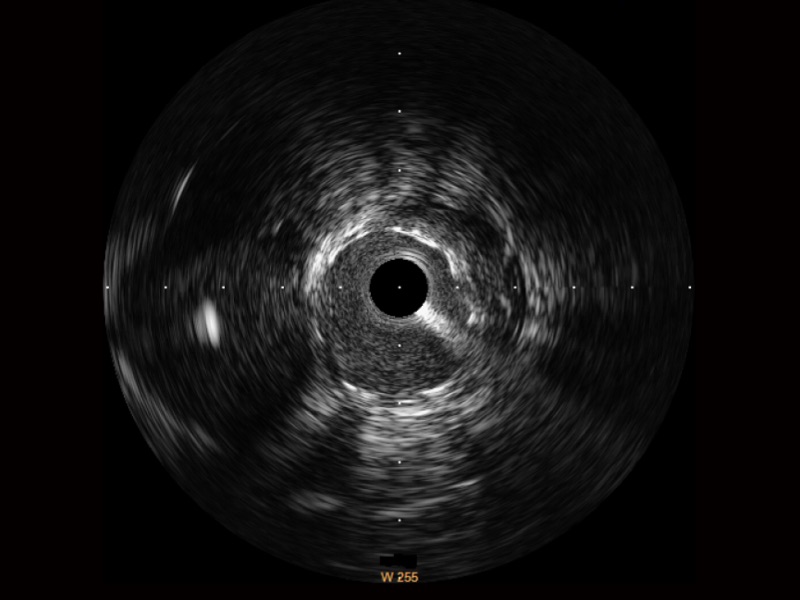

開(kāi)立寬頻IVUS圖像

傳統(tǒng)IVUS圖像

對(duì)比傳統(tǒng)IVUS導(dǎo)管成像,開(kāi)立寬頻IVUS圖像的近場(chǎng)支架梁顯影更細(xì)膩,遠(yuǎn)場(chǎng)中膜外血管仍清晰可辨,兼顧遠(yuǎn)中近,兼顧分辨力與穿透深度